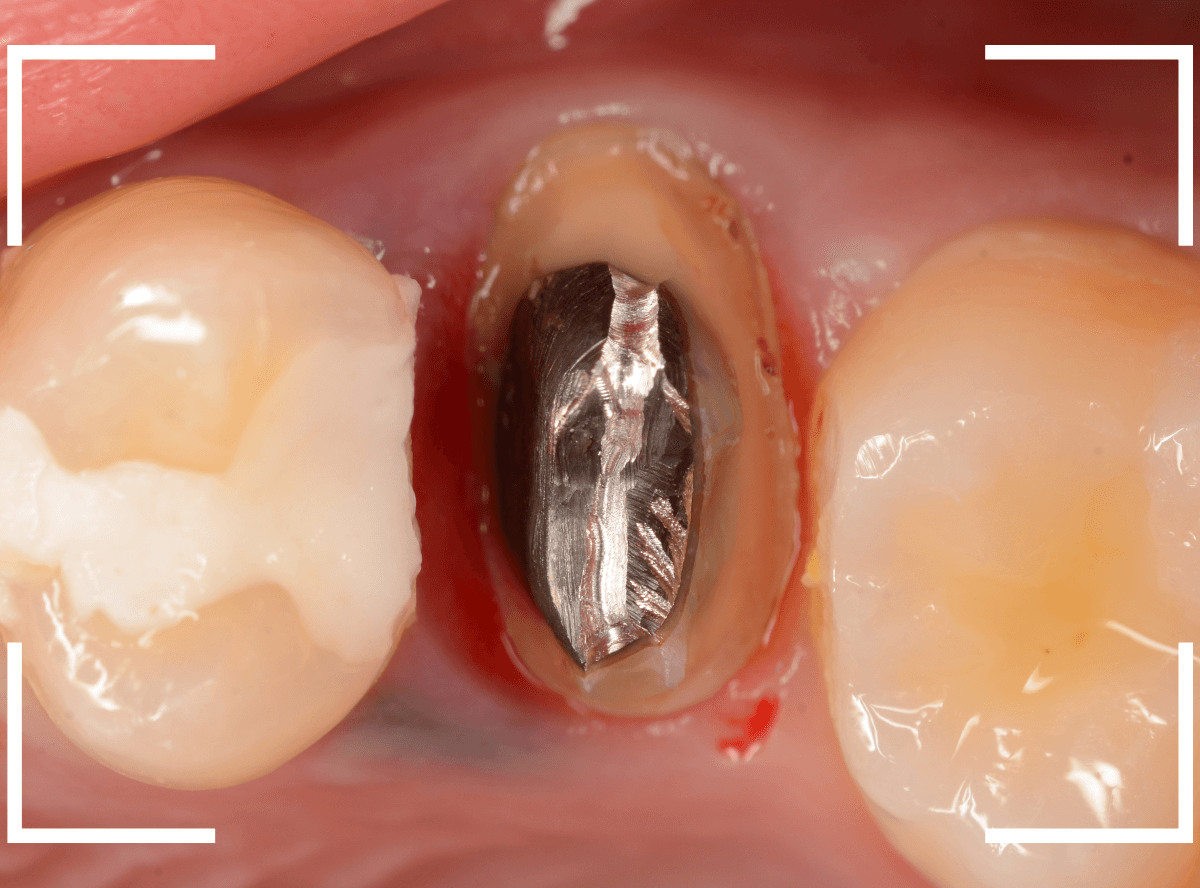

まず、土台の治療をしてから時間が経過していることと、不適合になっている事から、外して中を調べます。

すると、土台の中で虫歯にもなっていました。

(〇部の赤い部分)

こういった事は、レントゲン写真でもよくわからない事が多く、土台を外す治療は本当に神経を使います。

今回は、歯肉の中まで歯が欠損しているので、このまま土台とさし歯を作り直しても、いい結果にはなりません。

患者さんに状況を説明し、歯の周りの歯肉を麻酔をして電気メスでトリミングします。

このように歯の際が歯肉からしっかり出てる状況で製作しないと、さし歯はしっかりお口の中で安定しません。

この状態で新しい土台(ファイバー・コア)の型を取ります。